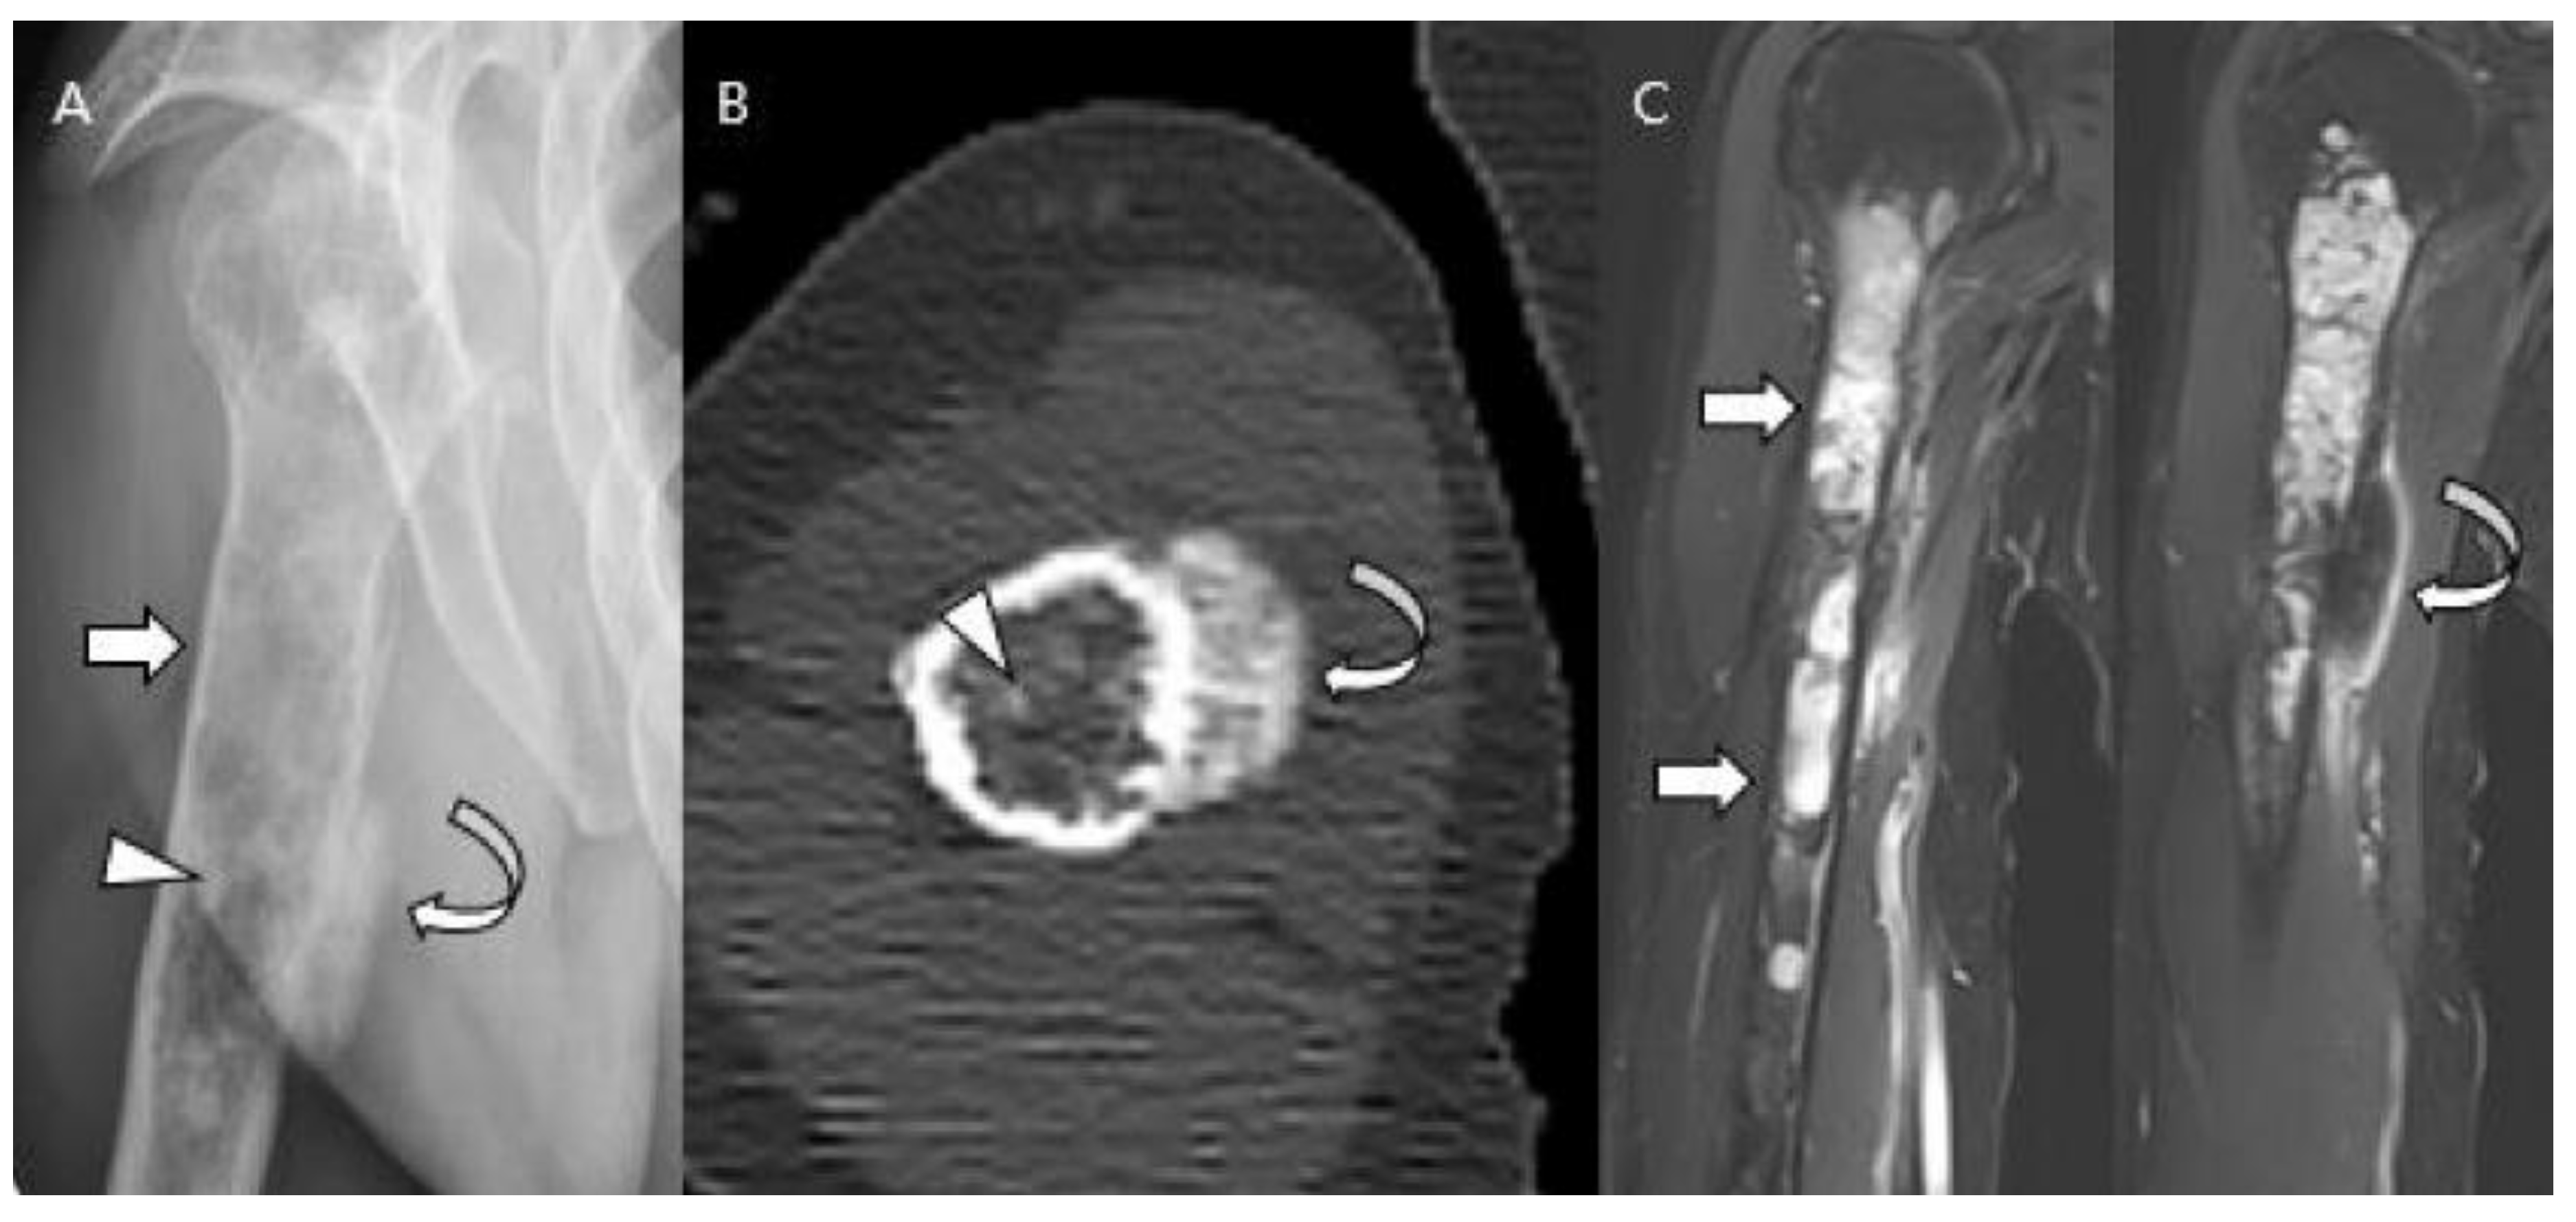

- Littrell, L.A.; Wenger, D.E.; Wold, L.E.; Bertoni, F.; Unni, K.K.; White, L.; Kandel, R.; Sundaram, M. Radiographic, CT, and MR Imaging Features of Dedifferentiated Chondrosarcomas: A Retrospective Review of 174 De Novo Cases. Radiographics 2004, 24, 1397–1409. [Google Scholar] [CrossRef]

- Saifuddin, A.; Mann, B.; Mahroof, S.; Pringle, J.; Briggs, T.; Cannon, S. Dedifferentiated chondrosarcoma: Use of MRI to guide needle biopsy. Clin. Radiol. 2004, 59, 268–272. [Google Scholar] [CrossRef]